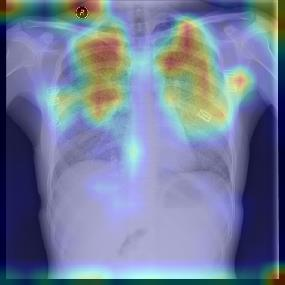

Chest X-ray (CXR) is the most typical diagnostic X-ray examination for screening various thoracic diseases. Automatically localizing lesions from CXR is promising for alleviating radiologists' reading burden. However, CXR datasets are often with massive image-level annotations and scarce lesion-level annotations, and more often, without annotations. Thus far, unifying different supervision granularities to develop thoracic disease detection algorithms has not been comprehensively addressed. In this paper, we present OXnet, the first deep omni-supervised thoracic disease detection network to our best knowledge that uses as much available supervision as possible for CXR diagnosis. We first introduce supervised learning via a one-stage detection model. Then, we inject a global classification head to the detection model and propose dual attention alignment to guide the global gradient to the local detection branch, which enables learning lesion detection from image-level annotations. We also impose intra-class compactness and inter-class separability with global prototype alignment to further enhance the global information learning. Moreover, we leverage a soft focal loss to distill the soft pseudo-labels of unlabeled data generated by a teacher model. Extensive experiments on a large-scale chest X-ray dataset show the proposed OXnet outperforms competitive methods with significant margins. Further, we investigate omni-supervision under various annotation granularities and corroborate OXnet is a promising choice to mitigate the plight of annotation shortage for medical image diagnosis.